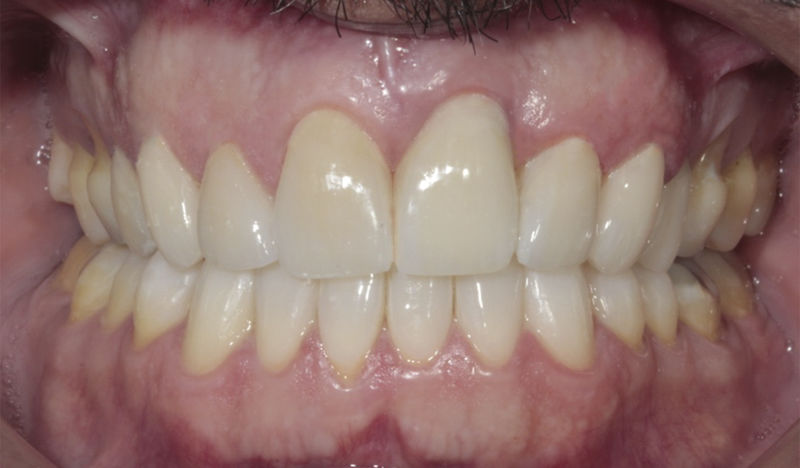

Implante fracasado, extracción, carillas, coronas y prótesis fija.